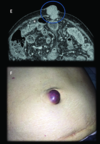

Q

If a patient develops portal hypertension (>5-10mmHg) this can cause portosystemic shunts. The 3 main places this occurs are superior portion of the anal canal, inferior portion of the esophagus and then round ligament (umbilical vein). What can portosystemic cause in the superior portion of the anal canal?

1 - fistula formation

2 - pilonidal sinus

3 - haemorrhoids

4 - diverticulitis

A

• enlarged veins that can bleed

How well did you know this?